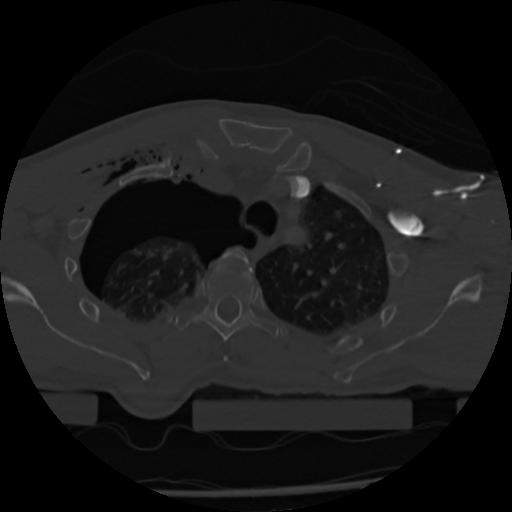

22 ANGIO,CE,Vol,0.5,ANGIO,,